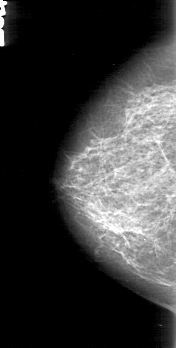

D_4162_1.LEFT_MLO

LEFT_CC LINES 5131 PIXELS_PER_LINE 2386 BITS_PER_PIXEL 12 RESOLUTION 43.5 OVERLAY

FILE: D_4162_1.LEFT_CC.OVERLAY

TOTAL_ABNORMALITIES 1

ABNORMALITY 1

LESION_TYPE CALCIFICATION TYPE PLEOMORPHIC DISTRIBUTION CLUSTERED

ASSESSMENT 0

SUBTLETY 4

PATHOLOGY MALIGNANT

TOTAL_OUTLINES 1

BOUNDARY